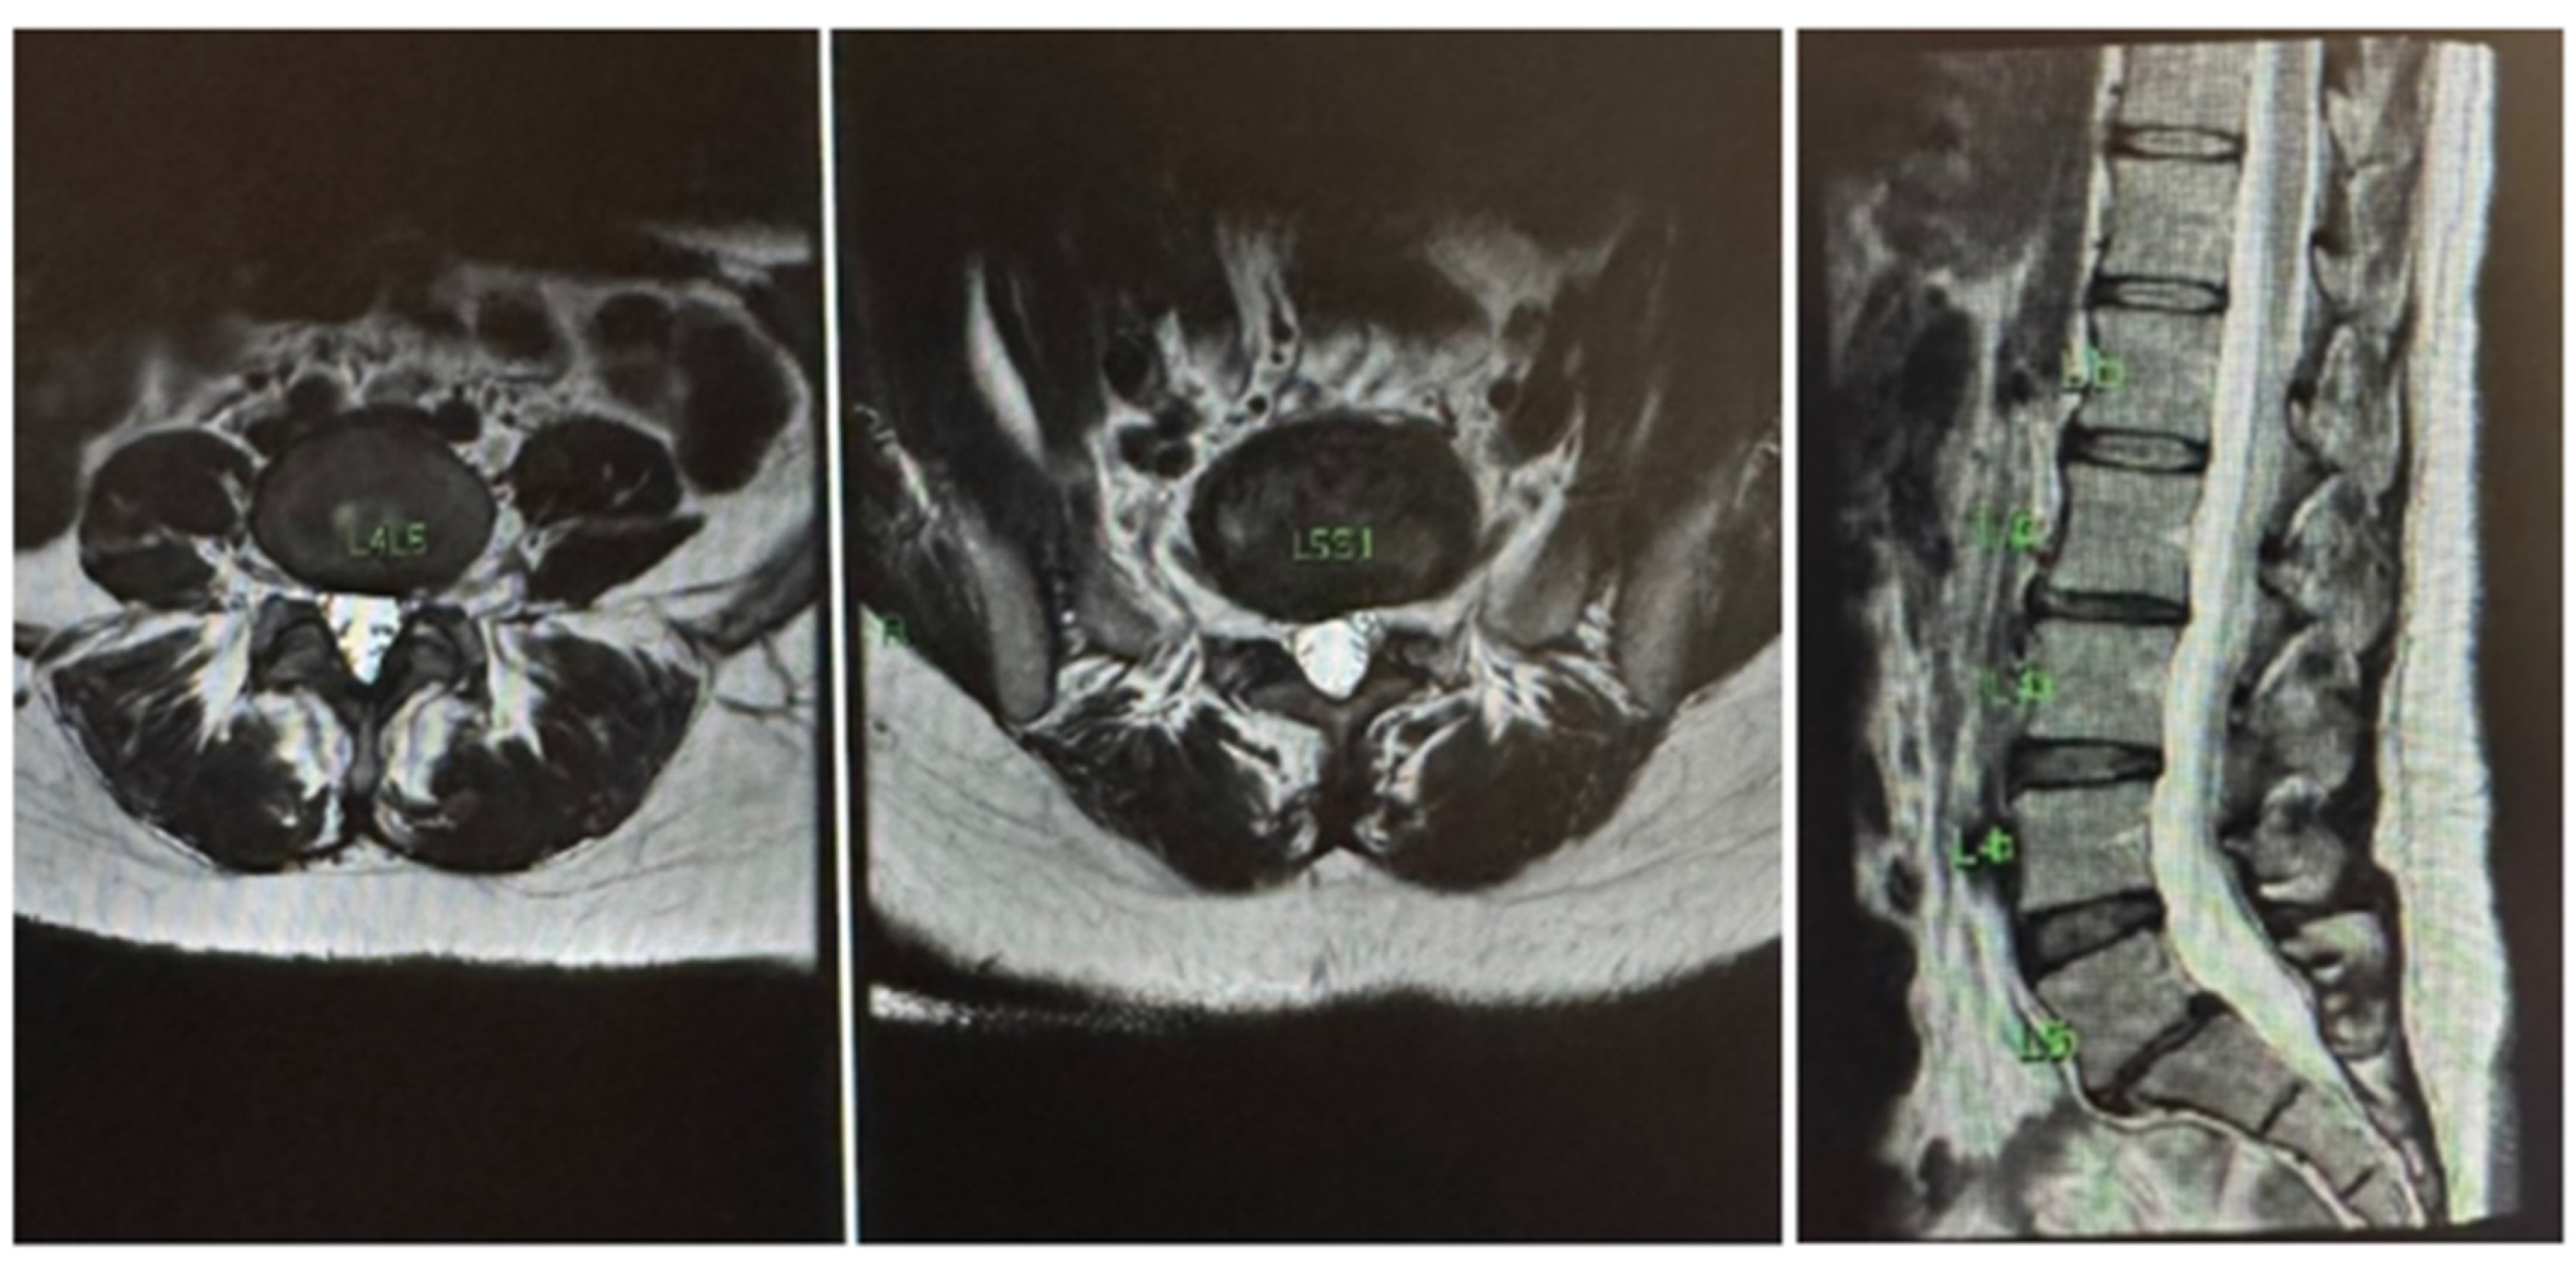

On physical examination, a positive Lasègue sign was noted at 30 degrees of MID elevation, with preserved reflexes but slightly decreased strength in the right leg (grade IV in the L5 and S1 myotomes). Paravertebral low back pain was present in the L4-5 and L5-S1 areas, with pain worsening during forced flexion of the spine, sitting, and with the Valsalva maneuver. Relief was reported with stretching and static standing. Segment degeneration was classified as Pfirmann IV, and the hernia was classified by the Michigan State University (MSU) system as 3B (Figure 1 A and B). MRI revealed a right paramedian extruded disc herniation at L5-S1 with dural and descending root compression of S1, along with segmental degeneration, an arthrosynovial cyst, and right isthmian lysis (Figure 1 C and D). Although surgery was recommended by other colleagues, the patient was highly reluctant to undergo any invasive procedure, including minimally invasive or endoscopic surgery, due to severe anxiety and an uncontrollable fear of needles. She was already receiving psychiatric care but remained unsuitable for interventions involving cannulas or needles.

Given these limitations and with her consent, we opted to apply transcutaneous STP Radiofrequency as a therapeutic alternative. Medium adhesive plates were placed on the lumbar spine at the level of the hernia and along the sciatic path in the right buttock, where the pain radiated. A Spring2® generator with medium patches was used, with the PRF STP set to 1.4A for 15 minutes, generating 108V (Figure 1E).

Figure 1. A) and B) Classification of herniated discs described by MSU (Michigan State University); C) Nuclear Magnetic Resonance demonstrating right paramedian L-S1 extruding hernia with compression of the dura and contact at the root of S1 on the right; D) Degeneration of the segment and isthmic spondylolysis on the righ; E) Example of TC-STP PRF being applied to the lumbar degenerative disc disease with radiculopathy.